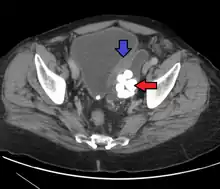

Transitional cell carcinoma, also called urothelial carcinoma, is a type of cancer that typically occurs in the urinary system. It is the most common type of bladder cancer and cancer of the ureter, urethra, and urachus. Symptoms of urothelial carcinoma in the bladder include hematuria (blood in the urine). Diagnosis includes urine analysis and imaging of the urinary tract (cystoscopy). Transitional cell carcinomas arise from the transitional epithelium, a tissue lining the inner surface of these hollow organs.[1] When the term "urothelial" is used, it specifically refers to a carcinoma of the urothelium, meaning a transitional cell carcinomas of the urinary system.

Diagnosis

Transitional refers to the histological subtype of the cancerous cells as seen under a microscope.